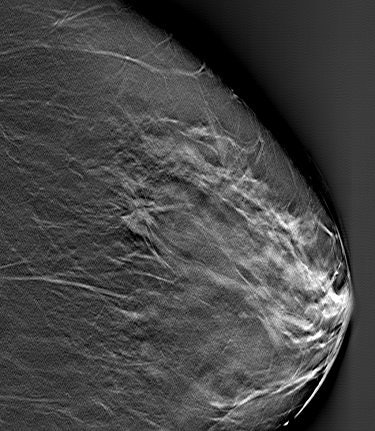

![]() |

| Patient who had previously undergone breast-reduction surgery. On left, surgical scars can be seen at the top half of DBT image. At right, tissue structures, which would have been partially obscured by the scar tissue, are visible. Images courtesy of Dexela and Mark B. Williams, Ph.D., University of Virginia, Charlottesville. |